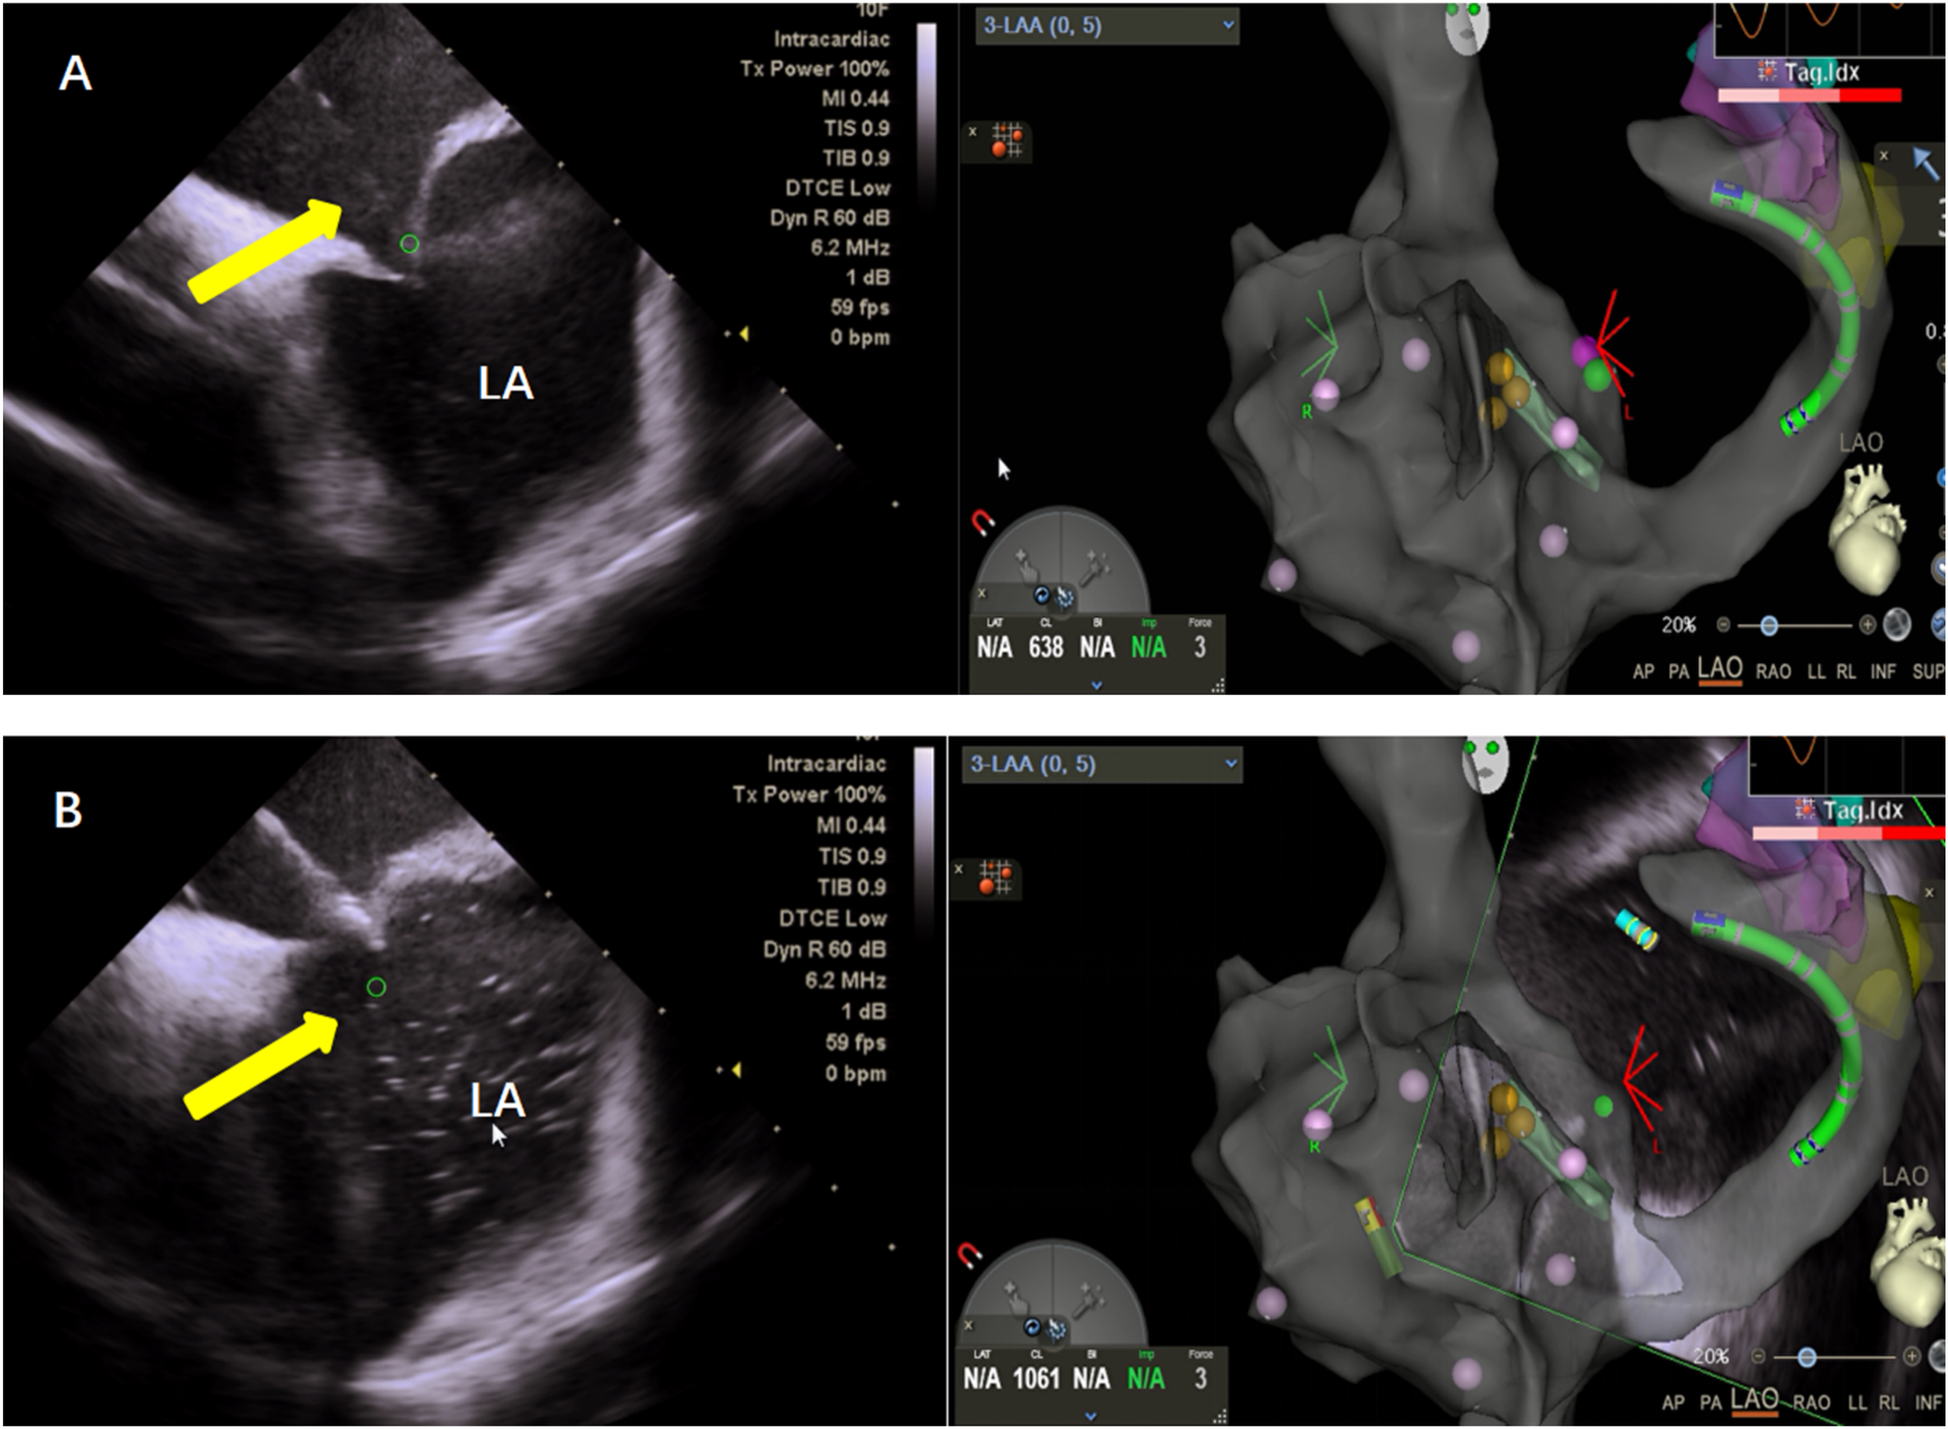

This study utilized the Carto electrophysiological navigation system (CARTO3, FG-5400-00C, USA) for cardiac modeling and ablation. Under intracardiac ultrasound guidance, a right atrial model was established, and three-dimensional fossa ovalis positioning was performed. Zero-ray transseptal puncture was carried out, and the SL1 sheath was advanced into the left atrium, as shown in Figure 2. Using the left atrial model for guidance, GP ablation was performed based on anatomical localization (temperature-controlled at 43°C, 40-watt discharge, with cold saline irrigation). During GP ablation, vagal responses including significant sinus bradycardia, sinus arrest, and atrioventricular block were observed, as shown in Figure 3. Ablation sites were marked, and ablated around these points reinforcely until vagal responses were no longer elicited. GP ablation was sequentially performed in the left superior GP (LSGP), left inferior GP (LIGP), right superior GP (RSGP), and right inferior GP (RIGP), as illustrated in Figure 2B. If five consecutive ablations within a GP region failed to induce any vagal response, the procedure proceeded to the next GP region. In most cases (80%), if the sinus rhythm gradually increased to approximately 90 beats per minute during ablation of the right superior pulmonary vein GP, ablation in that area was terminated at that point, as shown in Figure 4. The increase in sinus rhythm, disappearance of vagal reflexes, and completion of anatomical ablation signified the end of the procedure. Electrophysiological studies (EPS) demonstrated that the sinoatrial node recovery time and AV Wenckebach point were significantly shortened postoperatively compared to preoperative values, as shown in Figure 5.

Figure 2. (A) Zero ray puncture: intracardiac ultrasound (left), showing puncture of the atrial septum under the guidance of the right atrial model and three-dimensional visualization of a patent foramen ovale (right). (B) Saline was injected into the puncture needle under direct visualization with intracardiac ultrasound (left), confirming successful puncture of the atrial septum.